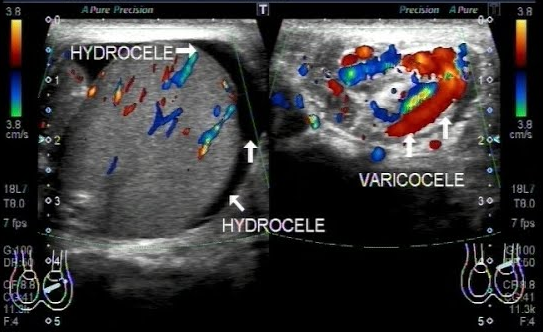

Smoking and testosterone supplementation can seriously reduce sperm count and motility exposure to chemicals such as lead and pesticides overheated testicles which can be caused by a varicocele, a condition in which the veins on a man's testicles are largely making them overheat, undescended testicles frequent exposure to heat that may result from wearing tight clothes, working in hot environments, the use of hot tubs or saunas, age, overweight or obesity, mental stress especially if it leads to reduced sexual activity, cancer treatment such as chemotherapy and radiation. Structural problems such as injury to the reproductive organs or blockage in the testicles.